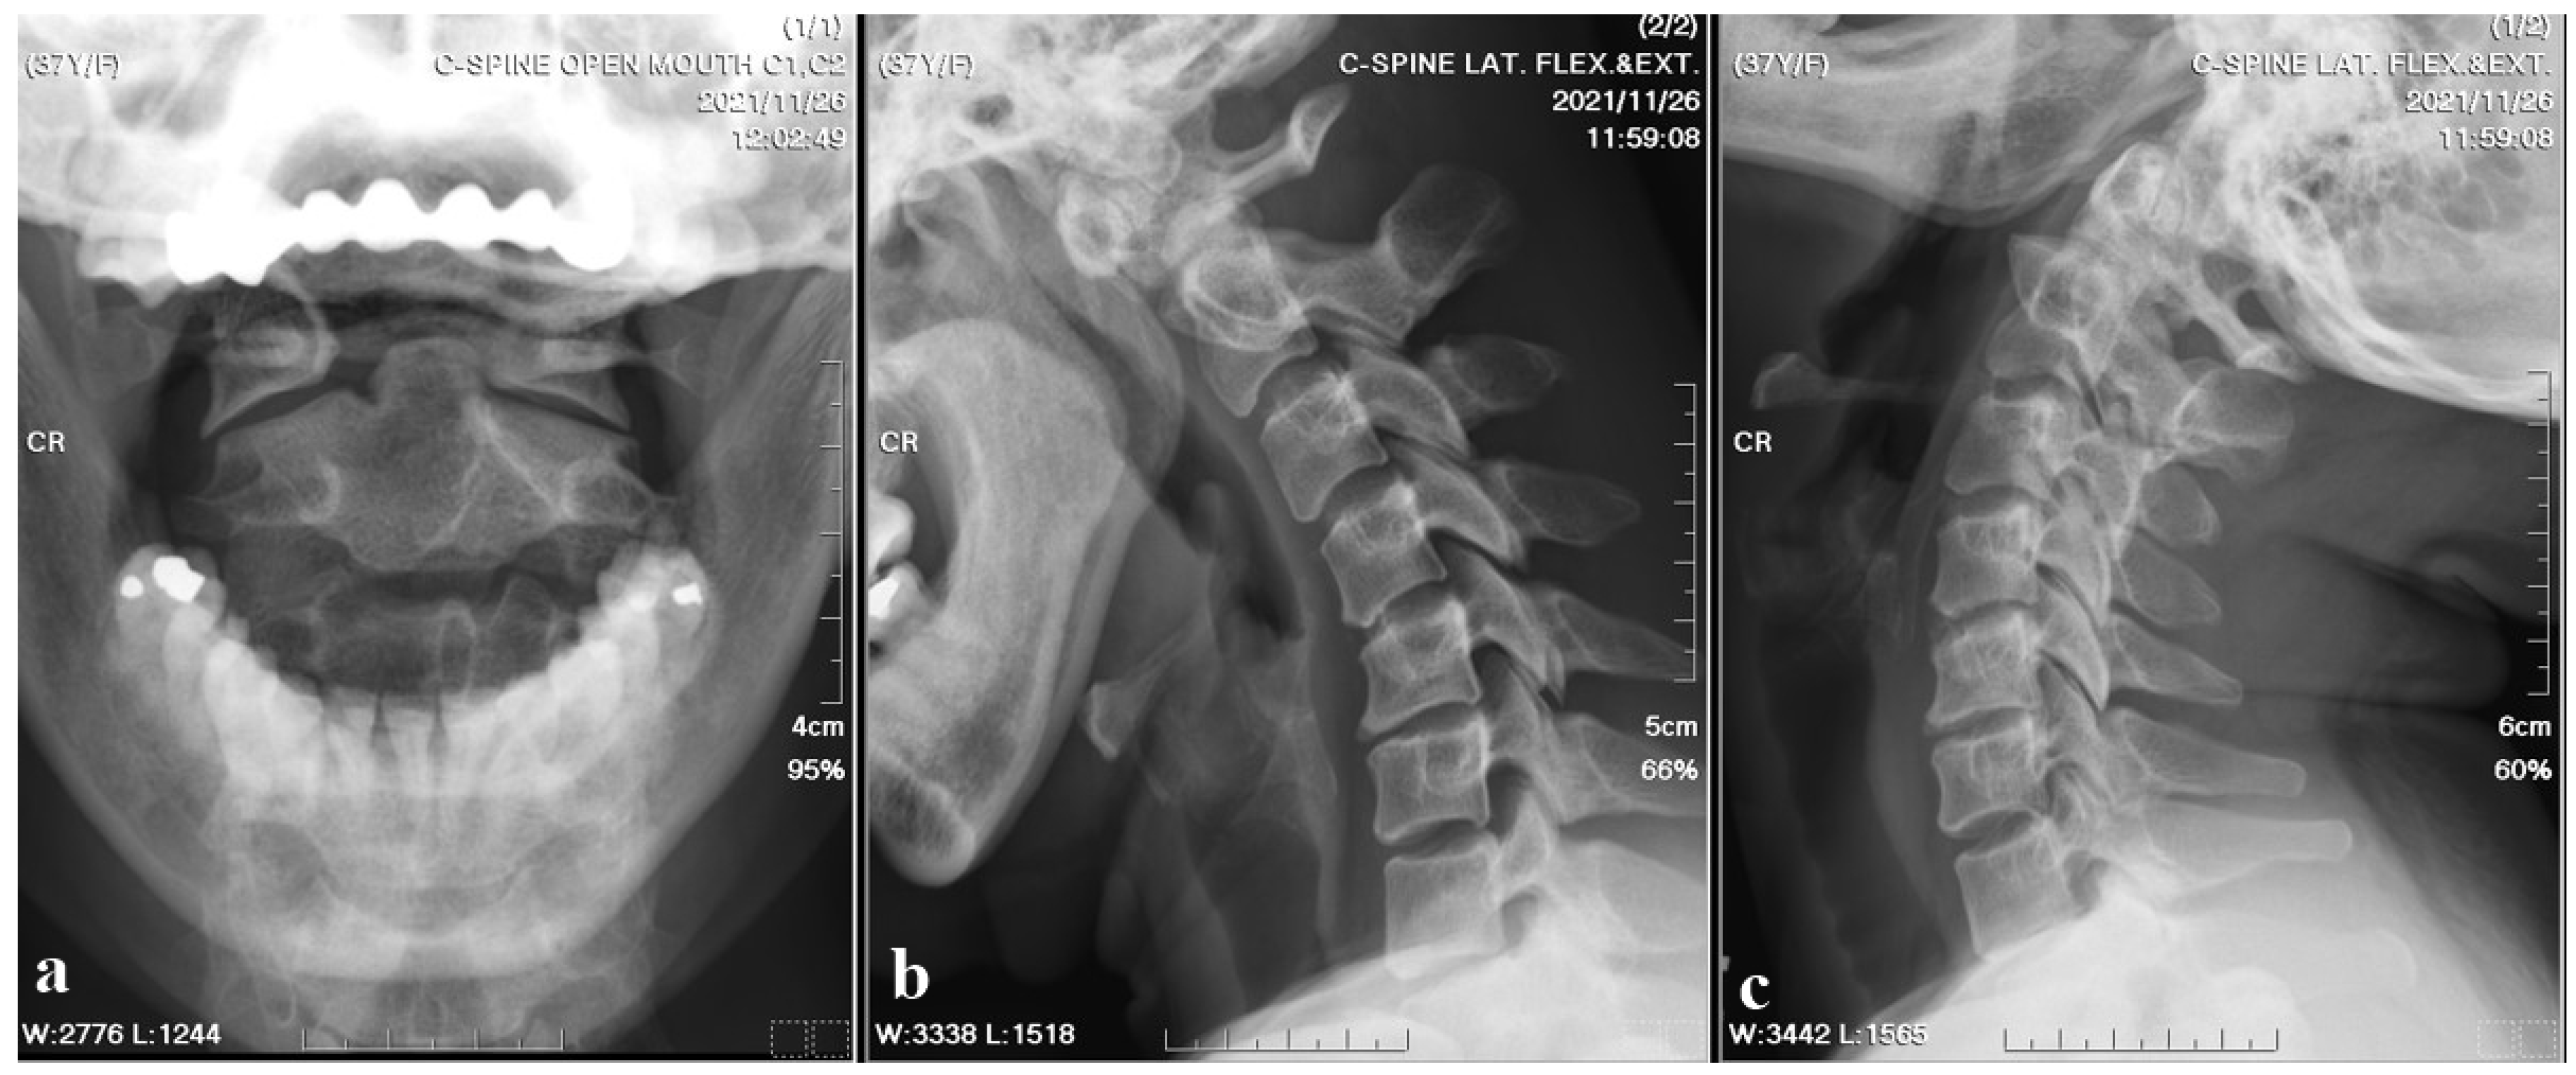

A 37-year-old female with no prior medical history or spinal surgeries presented to our neurosurgery outpatient department five months after a motorcycle traffic accident. Initially diagnosed with a C2 fracture at a local emergency department, she received only conservative treatment and wore a neck collar. Subsequent to the accident, she experienced persistent neck pain radiating to both shoulders and upper back, right-hand numbness with associated weakness, headaches, neck stiffness, and an unsteady gait. An initial cervical spine X-ray revealed the asymmetric widening of the distance between the right C1 arch and the dens with suspected atlantoaxial subluxation (Figure 1). Computed tomography revealed non-fused bony elements (Figure 2). Further cervical spine magnetic resonance imaging (MRI) (Figure 3) highlighted os odontoideum with C1-C2 subluxation and slight spinal cord atrophy at the C1-C2 level due to instability. There was also evidence of ventral compression at the C1-C2 level from chronic inflammatory pannus and granulation tissue.

Figure 2. Cervical spine CT bone window images. The sagittal view and coronal view revealed the non-fused C2 bony elements of the odontoid process.